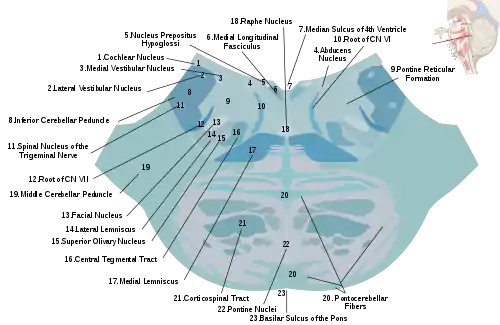

Nuclei

A number of cranial nerve nuclei are present in the pons:

- mid-pons: the principal sensory nucleus of the trigeminal nerve (V)

- mid-pons: the motor nucleus for the trigeminal nerve (V)

- lower down in the pons: abducens nucleus (VI)

- lower down in the pons: facial nerve nucleus (VII)

- lower down in the pons: vestibulocochlear nuclei (vestibular nuclei and cochlear nuclei) (VIII)

Median sagittal section of brain Nuclei of the pons and brainstem

Nuclei of the pons and brainstem Cerebrum. Deep dissection. Inferior dissection.